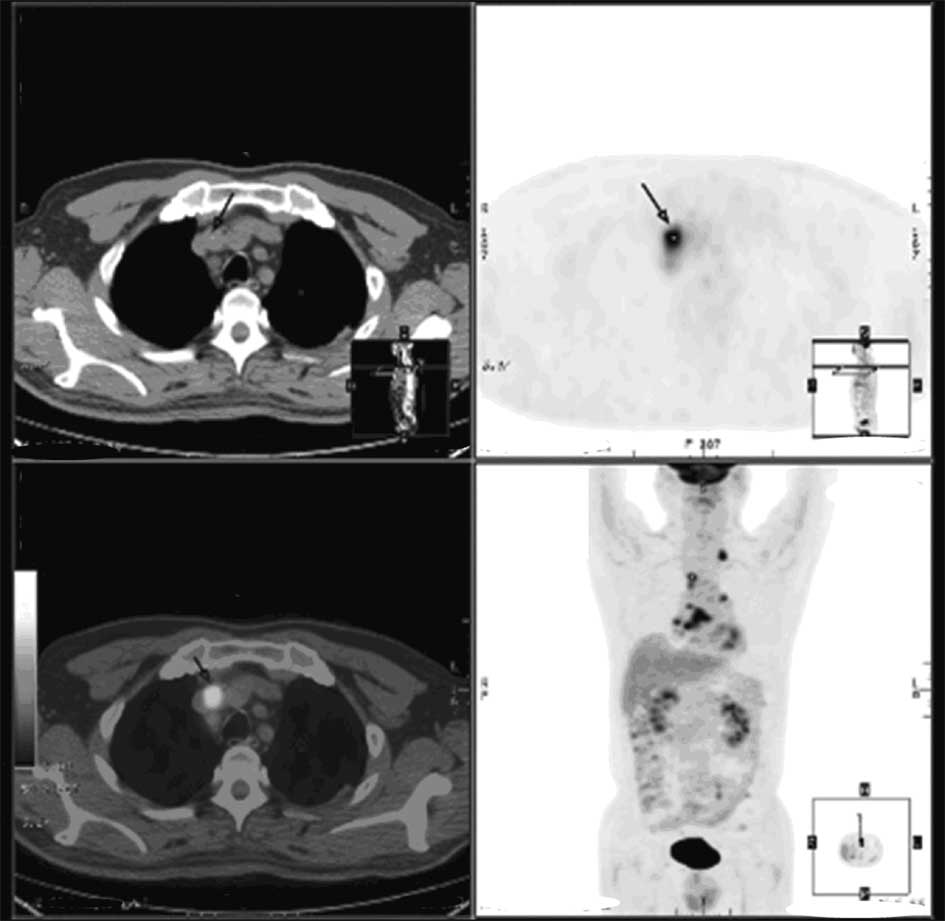

The current study reports the case of a 61‑year‑old man with diabetes who was suffering from generalized pain over the whole body and gradually progressive numbness. The patient was initially diagnosed with diabetic peripheral neuropathy and received treatment, however, the symptoms persisted. In October 2010, the patient was admitted to the Chinese People's Liberation Army Navy General Hospital (Beijing, China) for the treatment of diabetes, however, a full‑body sharp pain was also described, which was relieved upon massaging the area. Causes, other than diabetes, were investigated for these symptoms. Chest computed tomography and positron emission tomography‑computed tomography scans revealed a mass shadow in the right lower lobe of the lung, with multiple lymphatic metastases. Lung cancer was diagnosed with a tumor‑node‑metastasis stage of T1N3Mx. Following treatment of the cancer with chemotherapy and radiotherapy, the patient's symptoms were significantly improved. The present study reports a rare case of a paraneoplastic neurological syndrome (PNS) that presented as painful neuropathy resulting from lung cancer, which mimicked diabetic peripheral neuropathy.

Figure 1

Figure 2